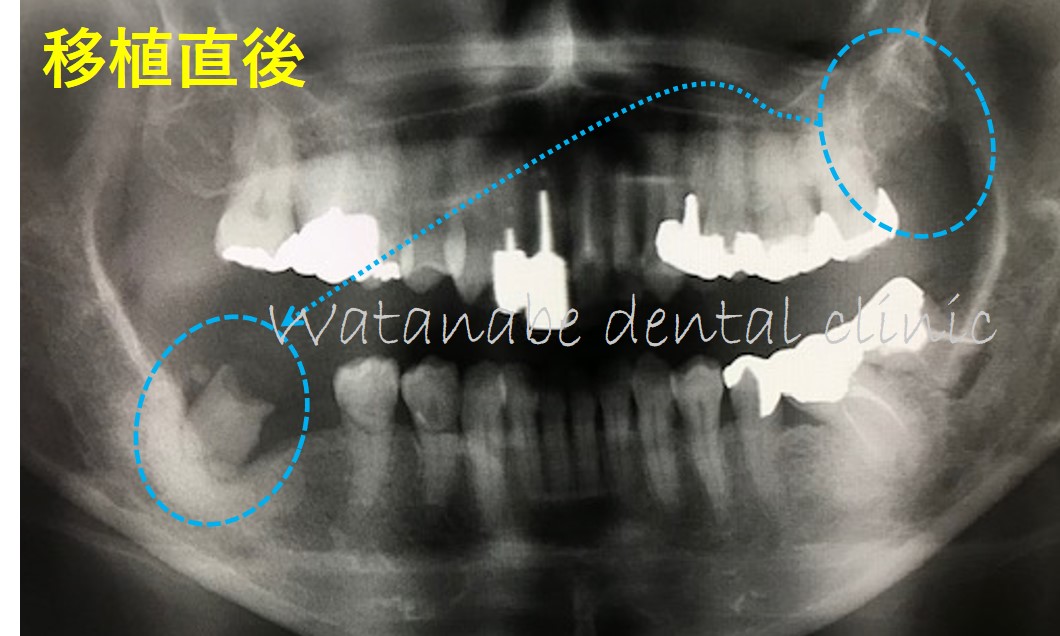

移植直後のエックス線所見です。